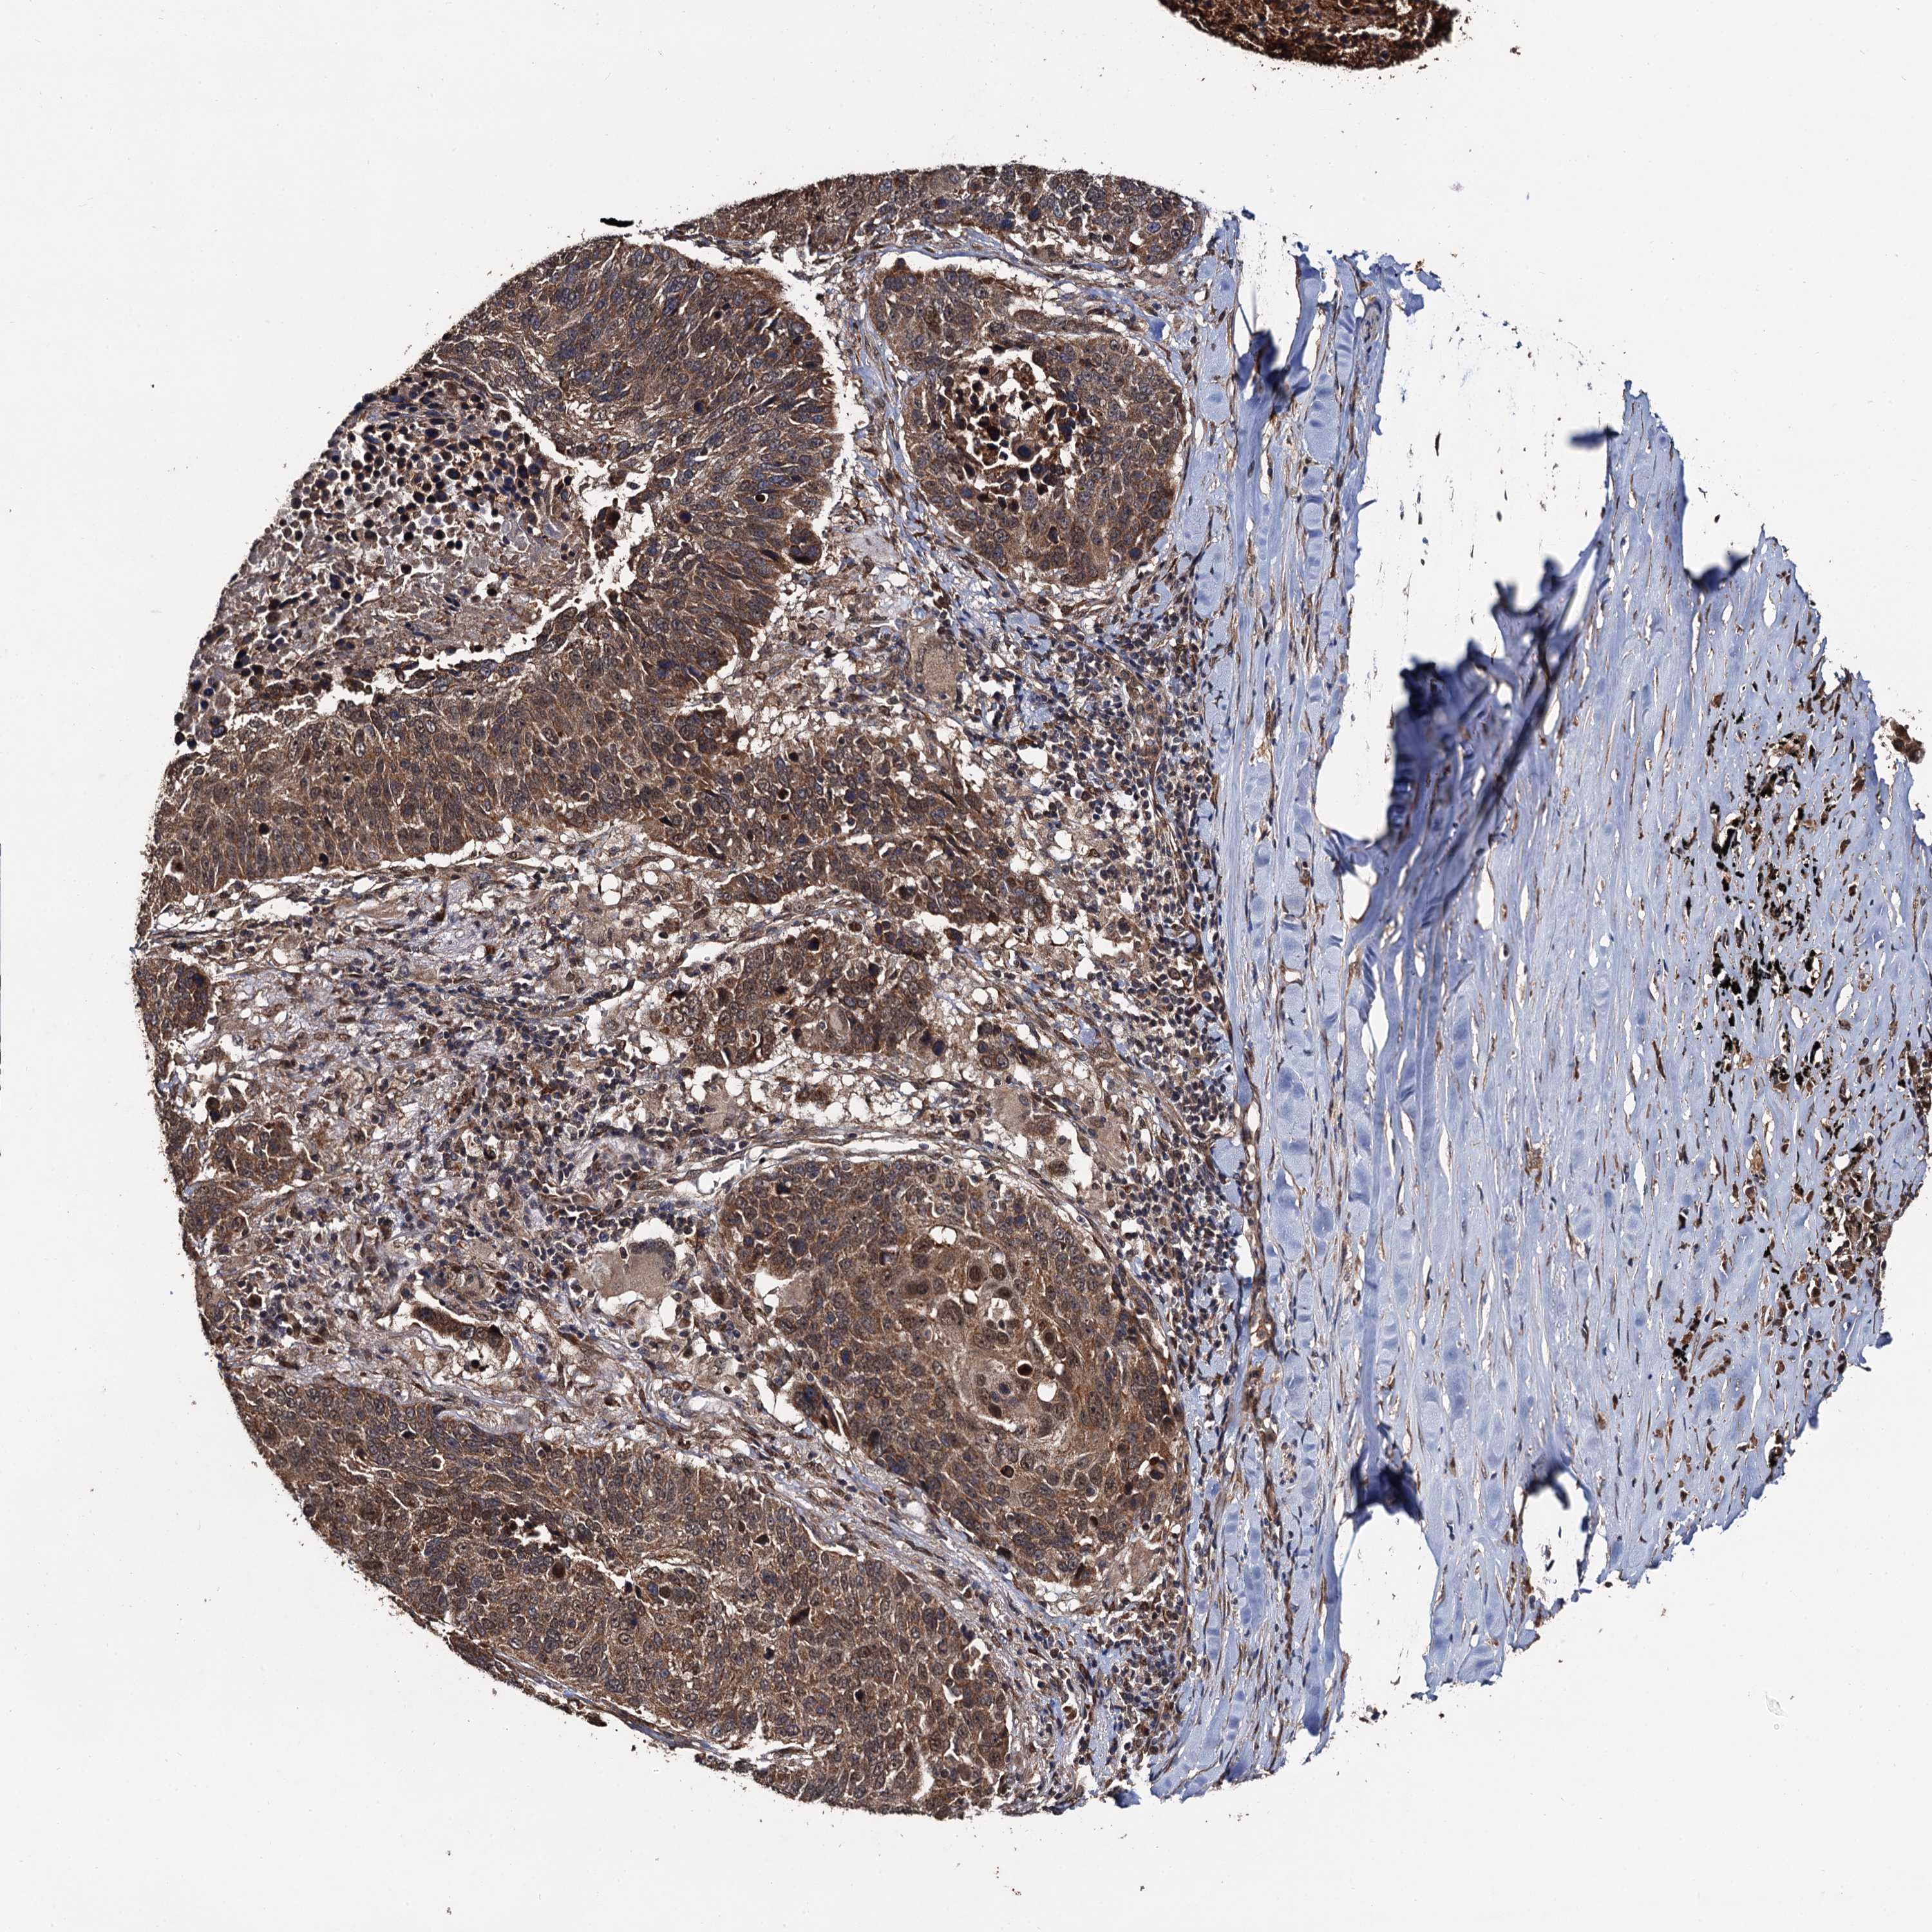

CANCER LUNG CANCER Show tissue menu

LUAD TCGA LUAD VALIDATION LUSC TCGA LUSC VALIDATION PROTEIN LUAD CPTAC PROTEIN LUSC CPTAC PROTEIN EXPRESSION

ANTIBODIES

AND

VALIDATION